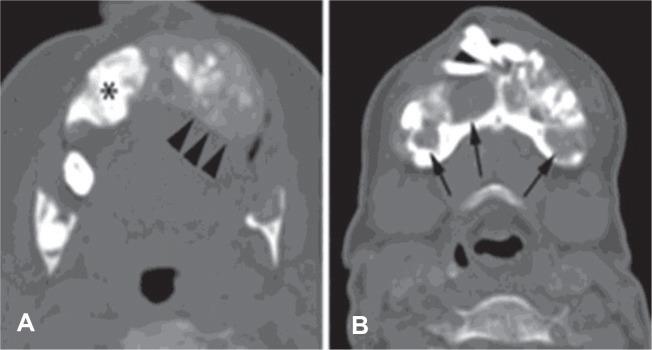

We present the rare case of a 47-year-old woman with protracted primary hyperparathyroidism complicated by communicating hydrocephalus and cerebellar tonsillar herniation secondary to calvarial thickening. The parathyroid glands remained elusive, despite the use of advanced preoperative imaging modalities and three neck explorations. The serum calcium was optimally controlled with cinacalcet and alfacalcidol. Awareness of this rare complication is essential for early diagnosis and prompt intervention to prevent fatal posterior brain herniation.